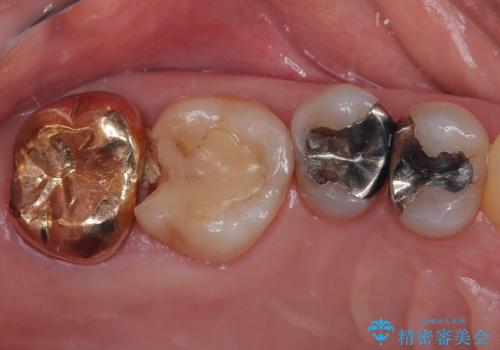

- 詰め物が欠けたとのことで来院された患者様です。来院時痛みはなく、食べ物が詰まる不快感がある状況でした。詰め物の範囲が大きくセラミックの被せもの(オールセラミッククラウン)での治療をご提案しましたが、患者様が歯はあまり削りたくないとのことで、リスクなどを説明したうえでセラミックの詰め物(ハイブリッドインレー修復)で治療していくことになりました。

拡大鏡視野下で、保険のプラスチック、虫歯の除去を行い、ハイブリッドインレーに適した形に整えました。